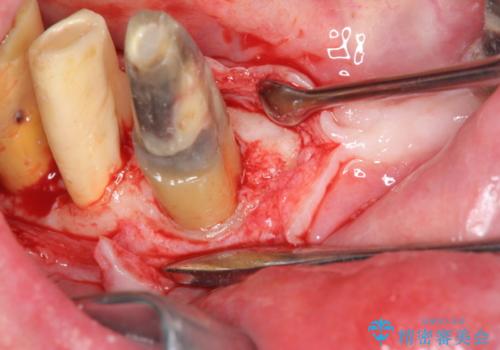

残すことのできない歯を抜去し、入れ歯になることを回避すべくブリッジ治療を行いますが支台となる歯の歯周病を改善すべく歯周病により溶けた歯槽骨の再生治療を計画します。

再生治療により良好な歯槽骨の再生が得られ、入れ歯ではなく取り外しの必要のないブリッジによる機能回復を行うことができました。